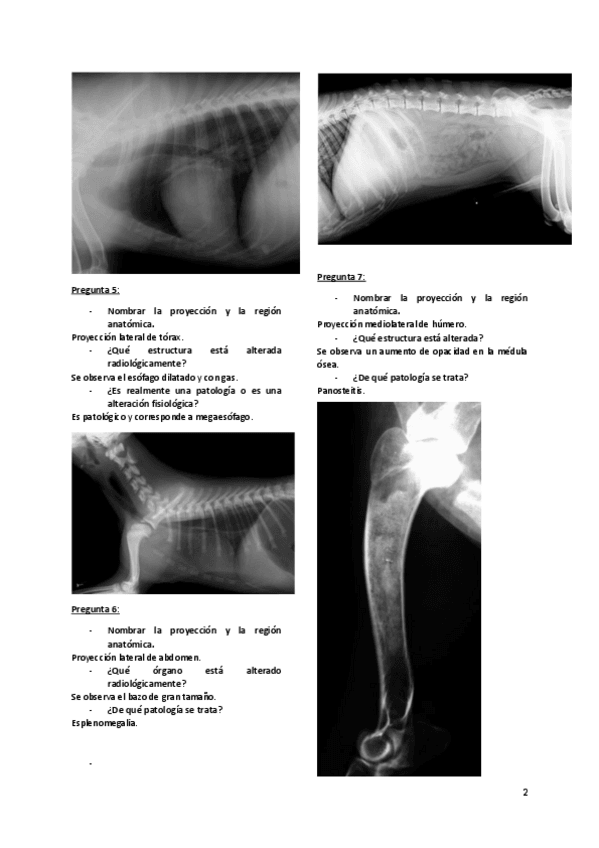

Imágenes de radiografias explicadas

He publicado nuevos apuntes de 3º Diagnóstico Por la Imagen: Imágenes de radiografias explicadas

Rx-abdomen.pdf

Rx-torax.pdf

Rx-cuello-y-torax.pdf